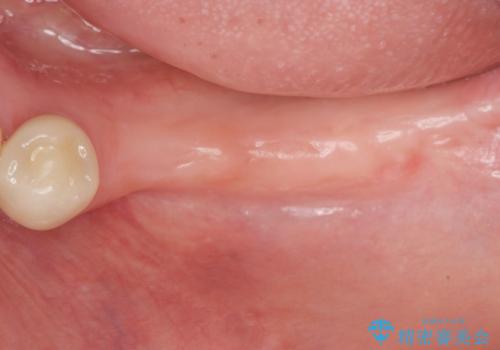

- 「奥歯がたくさん無くなってしまい、食事が楽しめるようにしっかりとかめるようにしてほしい。」という希望で来院されました。

入れ歯かインプラント治療の選択肢をご案内ししっかりと咀嚼機能を回復できる、インプラント治療を希望されました。

骨の量が比較的十分に保たれていたため、インプラントを埋入し1ヶ月後には仮歯を入れてしっかりと咬合機能を回復することができました。